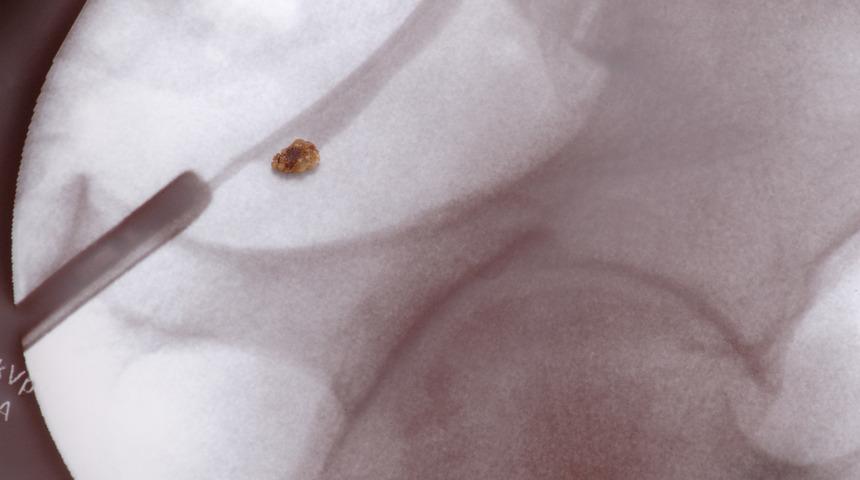

Böbrek taşı hastalığı son yıllarda yaygınlaşıyor! Korunmanın 7 yolu

Özellikle de gece saatlerinde şiddetli sancılarla uykudan uyandıran, yaşamı kabusa çeviren bir sorun; böbrek taşı. Halk arasında ‘idrar yollarından kum dökme’ olarak bilinen bu hastalık erkeklerde kadınlara göre iki üç kat daha fazla görülüyor. Peki, böbrek taşından korunmanın yolları nelerdir? İşte yanıtı...

Acıbadem Kozyatağı Hastanesi Üroloji Uzmanı Doç. Dr. Hakan Özveri, böbrek taşının en çok yetersiz sıvı alımından kaynaklandığını belirterek “Bununla birlikte, son yıllarda sağlıksız beslenme, aşırı tuz tüketimi ve yüksek proteinli diyetler yapılması da idrardaki mineral yoğunluğunun, böbreğin eritebileceğinden fazla miktarda olmasına ve böbrek taşları oluşumuna neden oluyor” diyor.Taşa bağlı bir idrar yolu tıkanıklığının, böbreklerde hızla ilerleyen bir enfeksiyona zemin hazırlayabildiğini, hastalarda ateş, üşüme ve titremenin de görülebildiğini belirten Doç. Dr. Hakan Özveri, böbrek taşı tedavi edilmediği takdirde ileride böbrek kaybına bile yol açabildiğini söylüyor. Doç. Dr. Hakan Özveri, böbrek taşından korunmanın 7 etkili yolunu anlattı, önemli uyarılar ve önerilerde bulundu.